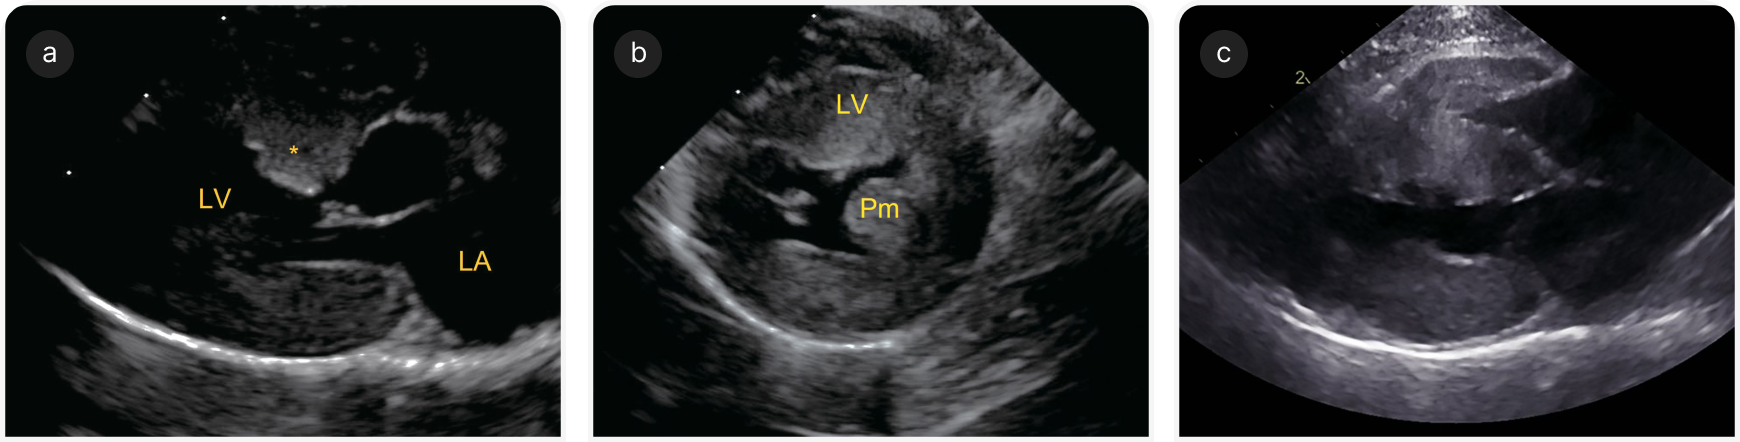

Гипертрофия ЛЖ при ГКМП у кошек может затрагивать как межжелудочковую перегородку, так и свободную стенку, либо изменения могут быть асимметричными, только с очаговым поражением, обычно в области основания межжелудочковой перегородки. Гипертрофия может также затрагивать правый желудочек, но ее характер и распределение у разных пациентов могут сильно различаться (Рисунки 1 и 2) (4).

Необходимо с помощью двухмерной эхокардиографии в правой парастернальной проекции в конце диастолы (момент до закрытия створок митрального клапана) оценить состояние межжелудочковой перегородки и свободной стенки ЛЖ (Рисунок 4a).

Необходимо следить за тем, чтобы не включить в измерения стенок папиллярные мышцы или области с выраженным утолщением эндокарда. Конечную диастолическую толщину стенки ЛЖ менее 5 мм считают нормальной, а ≥6 мм — гипертрофированной (14). Значения 5–6 мм остаются серой зоной, и их следует анализировать с учетом размеров тела, породы, других эхокардиографических переменных (16).